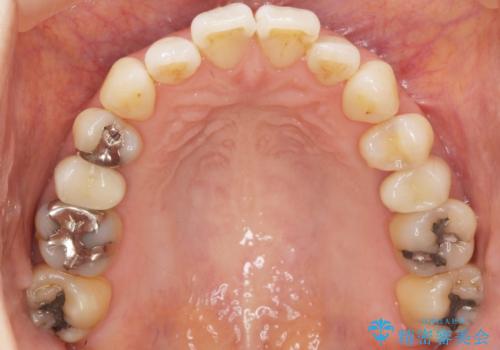

- 歯が欠けてしまったことを主訴に来院された患者様です。

欠けている奥歯(左上5)は失活歯で、保険内の銀の詰め物(メタルアンレー)で治療されていました。

金属の詰め物と土台を除去し、ファイバーコア(金属を使わない強くてしなやかな土台)を植立したのちセラミッククラウンによる補綴治療を行いました。

精査したところ、右上の奥歯(右上5)に根尖病変を認めたため、こちらは根管治療後にセラミッククラウンによる補綴を行いました。

自然な見た目と咬み心地にご満足頂けました。

オフィスホワイトニングを行い、白くなった天然歯に合わせたシェード(お色味)でクラウンを作製しました。